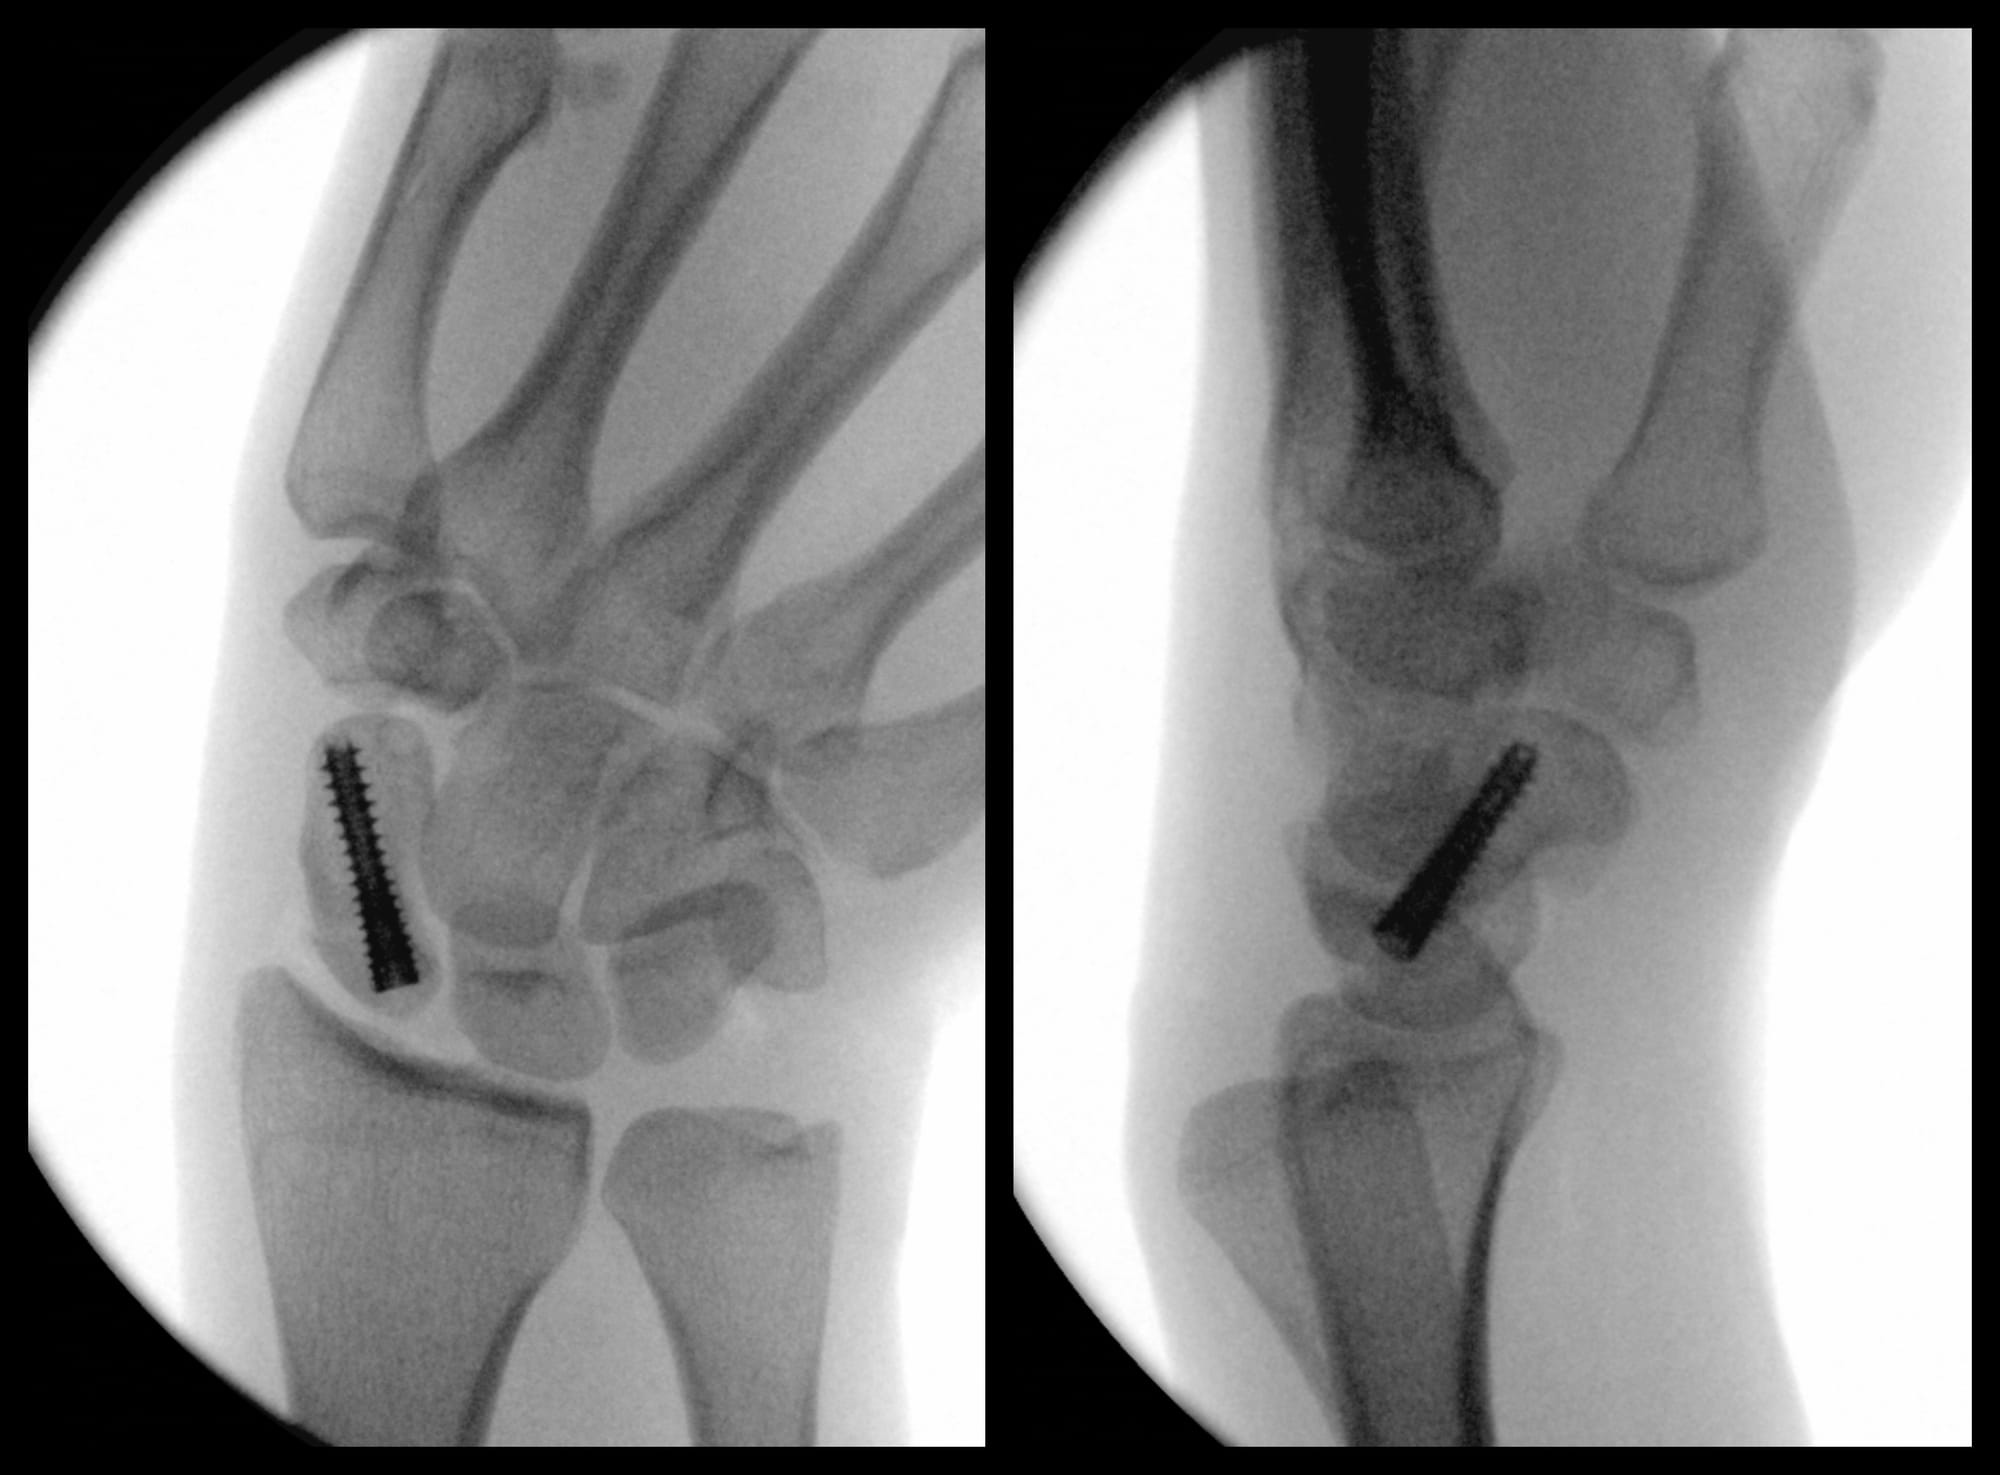

Scaphoid Fracture Fixation